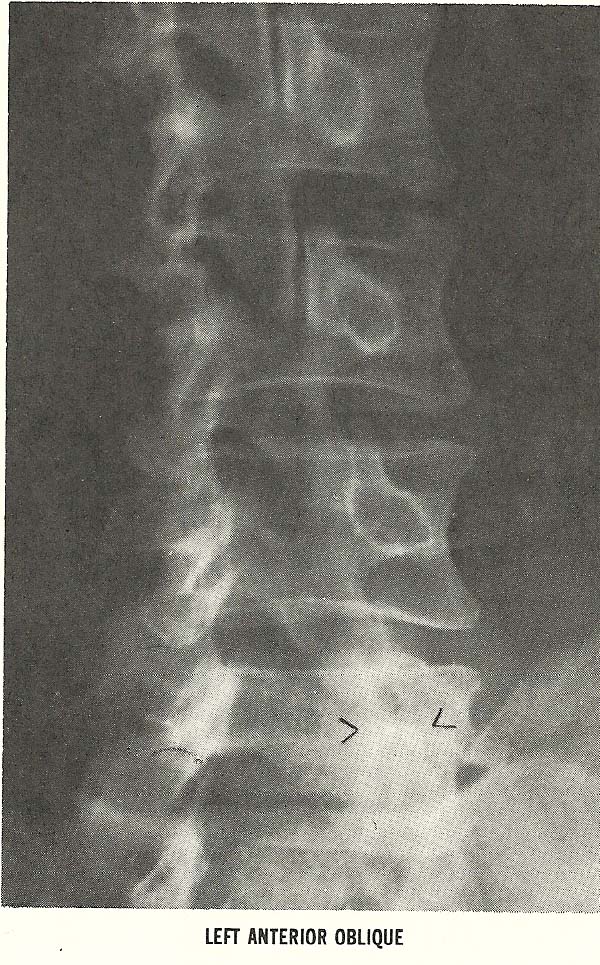

spacing (A-8). The rather marked intrusion and compromise of the neural

foramina at C4-C5, C5-C6, and C6-C7, seen on the left anterior oblique film

(Fig. 6.66), and similar alteration of the foramina at the same levels

are shown on the right anterior oblique film (Fig. 6.67), also meet the

criteria of subluxation under the classification of foraminal encroachment

(A-9).